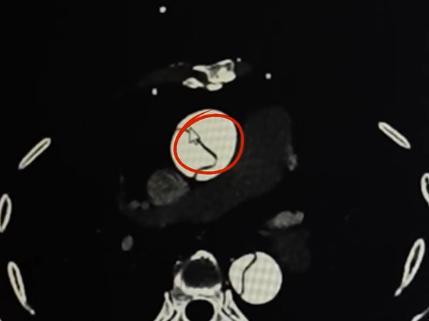

“患者是DebakeyⅠ型主動脈夾層,屬於最兇險的類型,升主動脈已撕裂,隨時可能破裂大出血。” 病人還在轉運路上,張總剛主任接到急診電話後,第一時間閱片評估,果斷啓動急診綠色通道。“每小時死亡率以1%遞增,48小時死亡率超50%,1周死亡率達75%,黃金治療時間是發病後6小時內!”。凌晨的醫院,他們在與生命賽跑——急診科、心臟大血管外科、手術室、麻醉科等多學科團隊迅速集結,術前準備同步推進。

什麼是主動脈夾層? 張總剛介紹,主動脈夾層是指心臟泵出的高壓血流撕破主動脈內膜,滲入內膜與外膜間形成 “假腔”。“假腔”外膜抗壓性極差,破裂後血液瞬間湧入胸腹腔,幾分鐘內即可致命;同時可能壓迫真腔,導致心、腦、腎等臟器缺血,引發心梗、腦梗、腎衰等嚴重併發症。